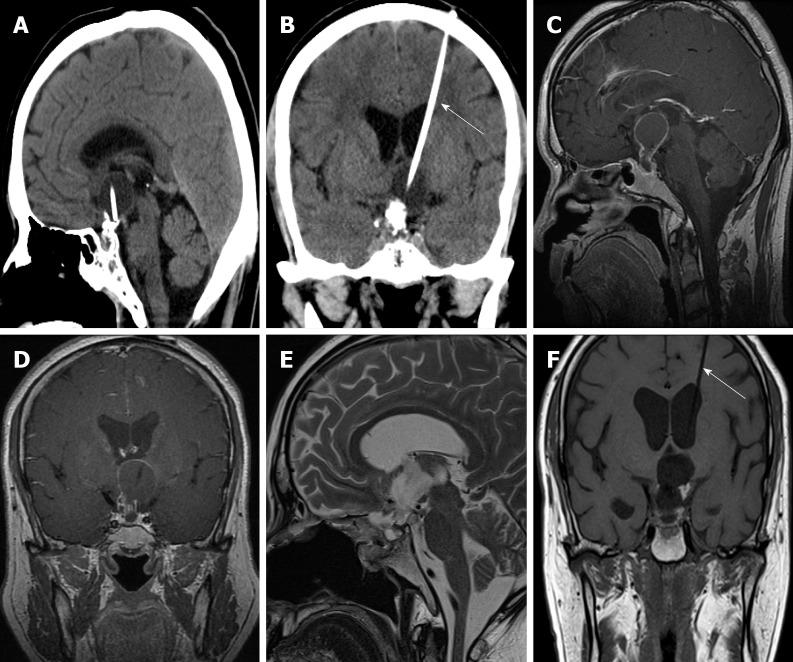

A 56-year-old man who underwent transsphenoidal surgery for craniopharyngioma 26 d ago presented gradual headache and cerebrospinal fluid leakage while vomiting 5 d post-discharge and required readmission to our department of neurosurgery. After admission, head imaging examination showed a hyperdense shadow in the superior sagittal sinus and right transverse sinus, edema at the bilateral parietal lobe, and hemorrhage at the left parietal lobe and right occipital lobe; the venous phase of cerebral angiography revealed CVST. The patient was treated immediately by intravenous thrombolysis, endovascular thrombolysis, and mechanical thrombectomy after the definite diagnosis. However, the neurological status of the patient continued to deteriorate and he died on the fourth day after readmission.

一名56岁男性在26天前接受了经蝶窦颅咽管瘤手术,出院5天后出现逐渐加重的头痛、脑脊液漏伴呕吐,需要再次入住我们神经外科。入院后,头颅影像学检查显示上矢状窦和右侧横窦高密度影,双侧顶叶水肿,左侧顶叶和右侧枕叶出血;脑血管造影静脉期显示CVST。确诊后立即对患者进行静脉溶栓、血管内溶栓和机械取栓治疗。然而,患者神经功能状态持续恶化,再次入院后第4天死亡。